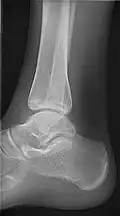

- Ankle - AP/Mortice and Lateral

-

Ankle - frontal -

15 degrees internal rotation -

Lateral (this one a bit suboptimal by not seeing straight through the ankle joint) -

Lateral oblique (to visualize the posterior border of the tibia)